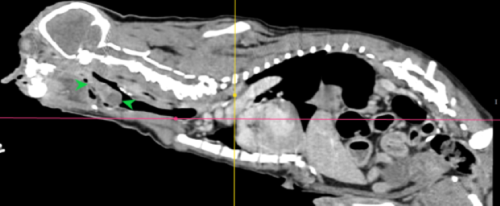

• 喉頭團塊 呼吸困難 急診

喉頭團塊 呼吸困難 急診